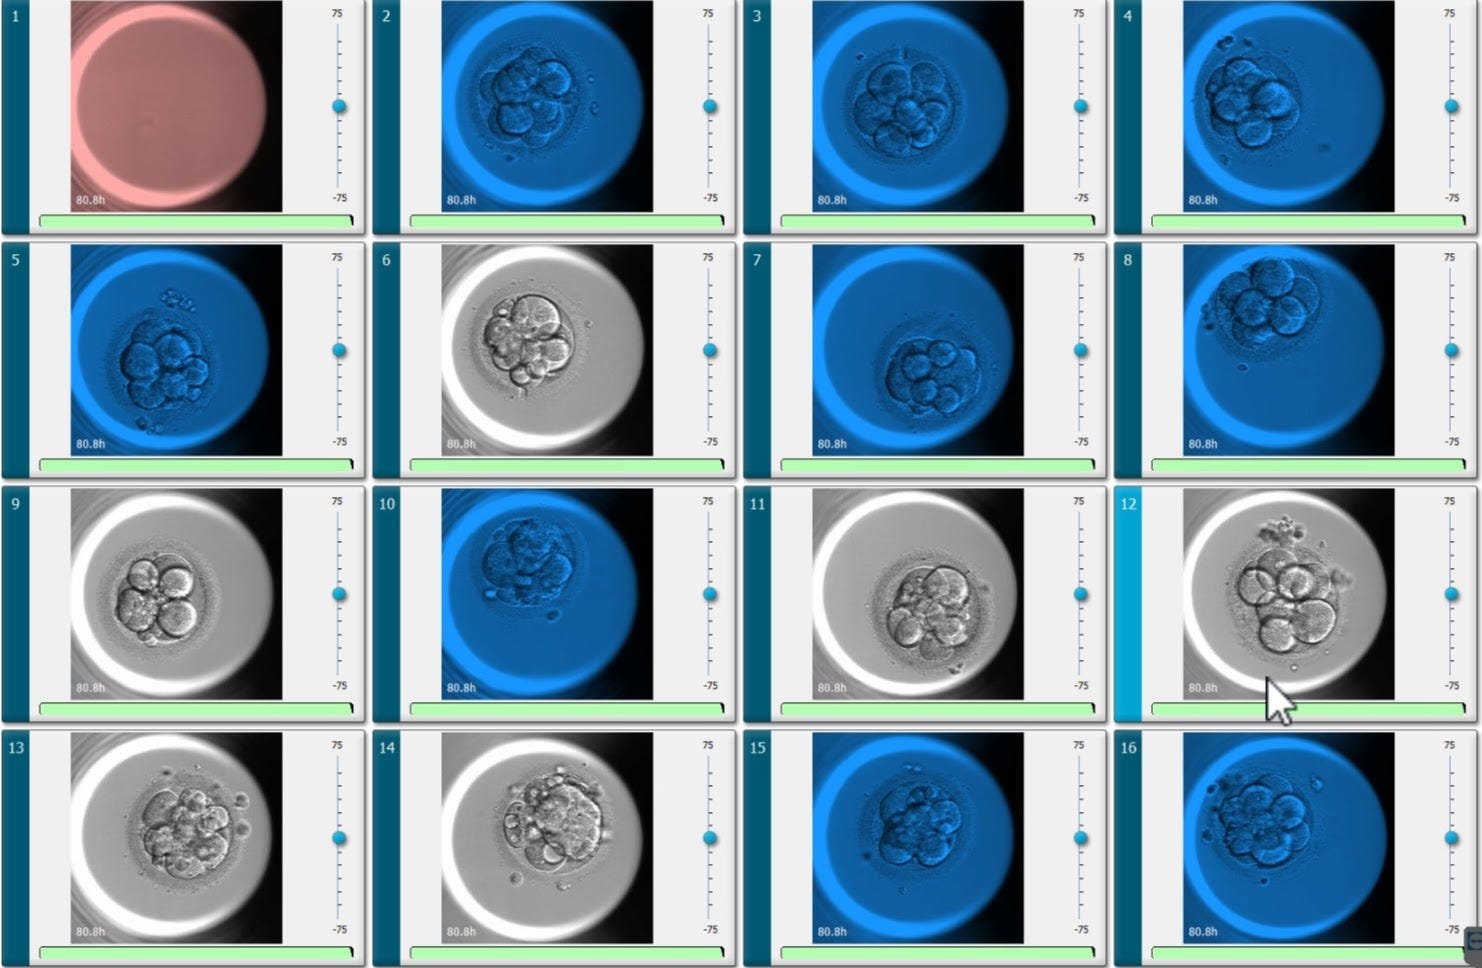

Of course, there was also still plenty of room for nature to have its say. My journey involved three intrauterine inseminations (IUIs), one miscarriage and finally one successful round of IVF. My retrieval yielded 22 eggs, but after fertilization and five days of development, genetic testing revealed only one viable embryo (my lovely daughter).